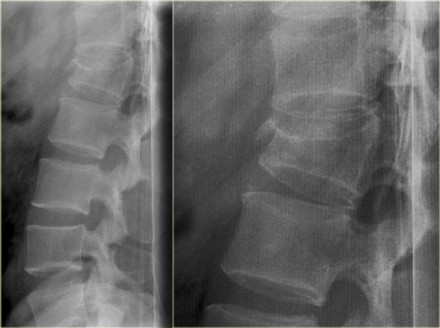

Jumper's fracture

On the left a fracture of the calcaneus and a lumbar spine fracture.

This is called a 'jumpers fracture' or a 'lover's fracture', because it is usely seen in people jumping out of a window to escape from the police or a jealous husband.

In this case it is clear that we are looking at an unstable fracture, because this is a burst fracture.

Both the anterior and the middle column are disrupted.

In addition there is edema in the posterior soft tissues indicating that there is also involvement of the posterior column.

Notice also the marrow edema in the adjacent bodies due to the severe axial loading.